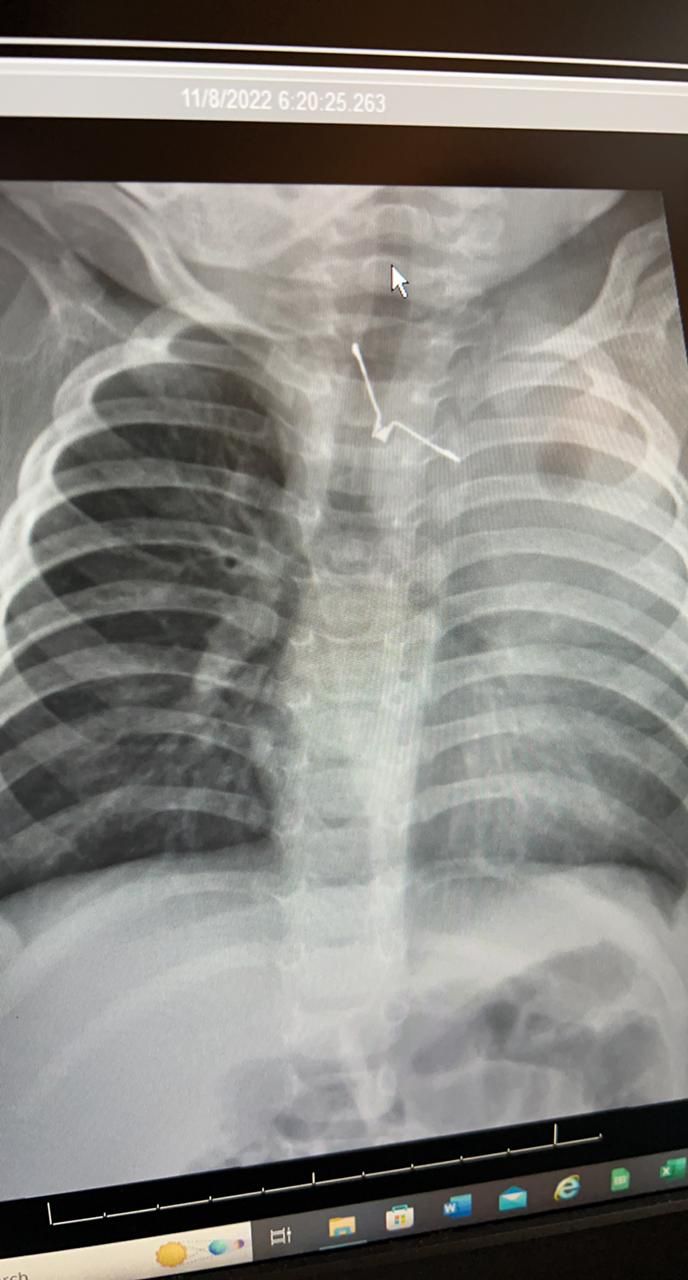

و أكدت أن الفريق الطبي المشرف على الحالة قام على الفور بعمل التحاليل و الاشعات اللازمة و إدخال الطفلة لغرفة العمليات بصفه عاجلة و ذلك لإكتشاف جسم معدني حاد الاطراف بلعته الطفله و بقي عالقاً في المرىء مسبباً لها مضاعفات صحية خطيرة خصوصاً لو تم تحريكه بأي طريقه خاطئه ، حيث نجح الفريق الطبي في مده زمنية تقارب الـ ( 4 ) ساعات من اخراج الجسم الغريب بالمنظار و بحذر شديد حتى لا تصاب الأنسجة المحيطة به بأي جروح ، و تتمتع المريضة بصحة جيدة تحت العناية المكثفة لإكمال فترة الشفاء .